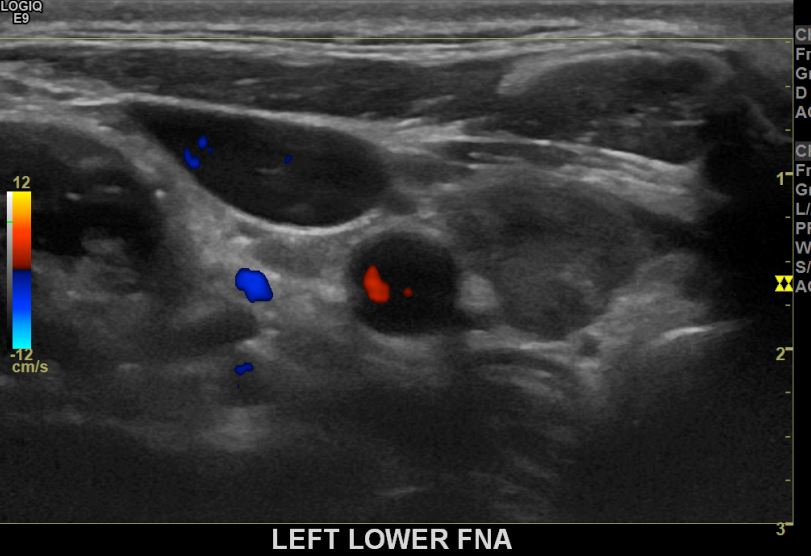

상기환자 외부검사 이상소견으로 정밀검사위해 내원하신 20대후반 여성분으로 의심스러운 좌엽혹 세포검사진행후 갑상선암으로 진단되었습니다